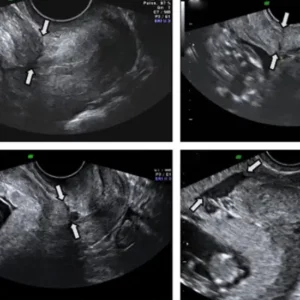

Ultrasound TVS (Transvaginal Scan)

Ultrasound Transvaginal Scan (TVS) is a specialized imaging technique primarily used in gynecology to examine the pelvic organs, particularly in women. During a TVS, a small transducer probe is inserted into the vagina, allowing for close proximity to the reproductive organs such as the uterus, ovaries, and fallopian tubes. This proximity enables high-resolution imaging, providing detailed views of the pelvic anatomy. TVS is commonly employed to diagnose conditions such as ovarian cysts, uterine fibroids, endometrial abnormalities, and to monitor early pregnancies. It is often preferred for its ability to produce clearer images compared to abdominal ultrasound, especially in cases where precise visualization is crucial. While the procedure may cause minor discomfort, it is generally safe, minimally invasive, and offers valuable diagnostic information for various gynecological conditions.